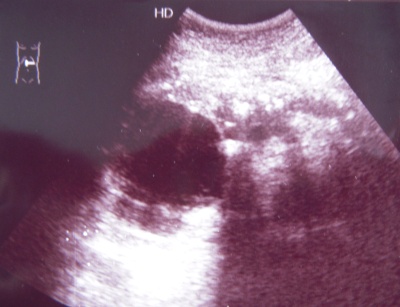

Молодой мужчина 35 лет, поступивший в отделение токсикологии ( после празднования очередной годовщины великой октябрьской социалистической революции), жалуется на боли в животе, тошноту, резкую слабость.

- узи 005з.jpg (45.28 КБ) 1504 просмотра

А врт снимок не очень...Вижу кисту в головке ПЖ,а вот саму железу,к сожалению,не вижу...Но подазреваю наличие панкреатита.С.В. сказал бы "нельзя исключить панкреатит"

Вижу хр.калькулезный панкреатит (и к анамнезу подходит

) и киста головки панкреас.